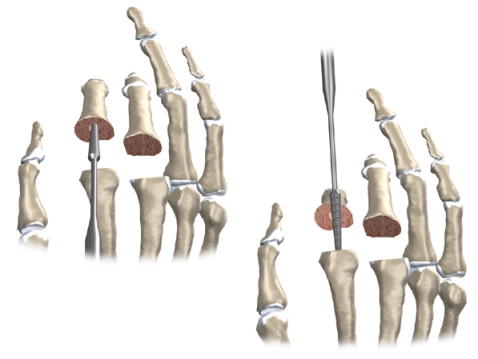

An incision is made across the back of the finger joints that are to be replaced. The soft tissues are spread apart with a retractor. Special care is taken not to damage the nearby nerve that passes by the joint. The joint is exposed. The ends of the bones that form the finger joint surfaces are taken off, forming flat surfaces.

A burr (a small cutting tool) is used to make a canal into the bones that form the finger joint.

The surgeon then sizes the stem of the prosthesis to ensure a snug fit into the hollow bone marrow space of the bone. The prosthesis is inserted into the ends of both finger bones.